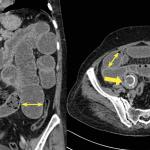

Cystite emphysémateuse

Une patiente de 89 ans, sans antécédent majeur, consulte aux urgences à la suite d’une chute accidentelle avec fracture...